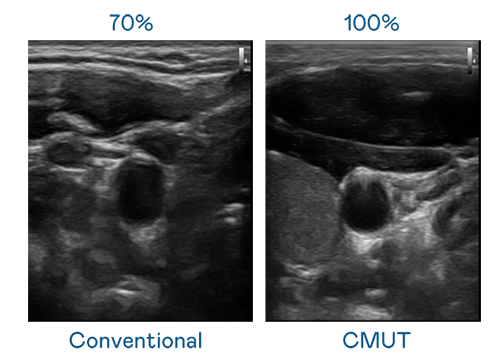

CMUT 技术是一种用电容式微机电元件来产生超音波讯号的技术。与传统 PZT 压电式技术相比,CMUT 频宽增加 30%,更宽频的超音波讯号让影像解析度大幅提升,是实现高影像品质医疗超音波扫描、促进精准医疗发展的关键技术。

超音波影像的解析度高低,首先取决于探头能发出的讯号频宽。一个好妈妈2韩剧蘑菇 CMUT 可提供高清晰的超音波讯号,提供高频宽、高灵敏度、影像纹理细节更高的超音波影像,协助医护人员缩短影像判读时间及利用精准的医疗影像进行诊断。